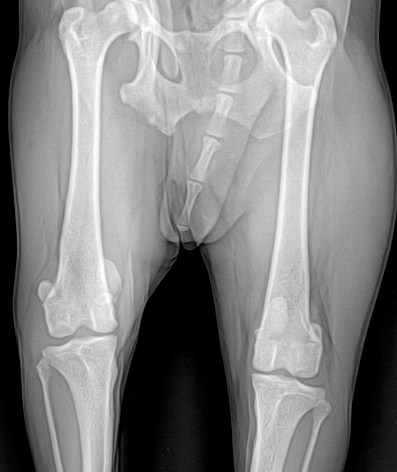

전십자인대 파열은 반려견에서 가장 흔한 무릎 관절 질환으로, 심할 경우 보행이 어렵고 심한 통증을 유발합니다. 본원은 뼈 구조, 체중, 활동 수준 등을 고려하여 TPLO, CTWO 등 다양한 수술 방법 중 가장 적합한 수술법을 선택해 맞춤 치료를 진행합니다. X-ray와 CT 영상을 통해 인대 손상 정도와 관절 상태를 정밀하게 진단하고, 수술 전 시뮬레이션을 통해 오차를 최소화합니다. 수술 후에는 통증 관리와 재활 운동, 근력 강화 프로그램을 통해 기능 회복을 돕고 재발을 예방합니다.

슬개골 탈구는 무릎관전의 해부학적 정렬 이상으로 인해 보행장애와 만성 통증을 유발합니다. 본원에서는 정밀한 보행 분석과 촉진, X-ray 및 필요 시 CT 기반의 골격 정렬 평가를 통해 탈구의 위치와 정도, 주변 연부조직과 골 변형 여부를 종합적으로 판단합니다.